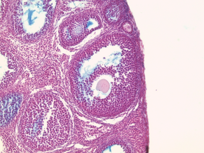

M. Suarez, E. Meinke, V. Romero and Z. Craig, 2026, 'Craig Lab: Mus Musculus Donor APOS001AB Antral Follicles Alcian Blue Slide 1L', https://mother-db.org/MDB0000520, Multispecies Ovary Tissue Histology Electronic Repository, Retrieved: January 15, 2026

Accession #: MDB0000520

Ovary position: unspecified

Location: follicle

Section thickness: 5 microns

Fixation: Formalde-Fresh Solution

Stain: Light microscopy stain